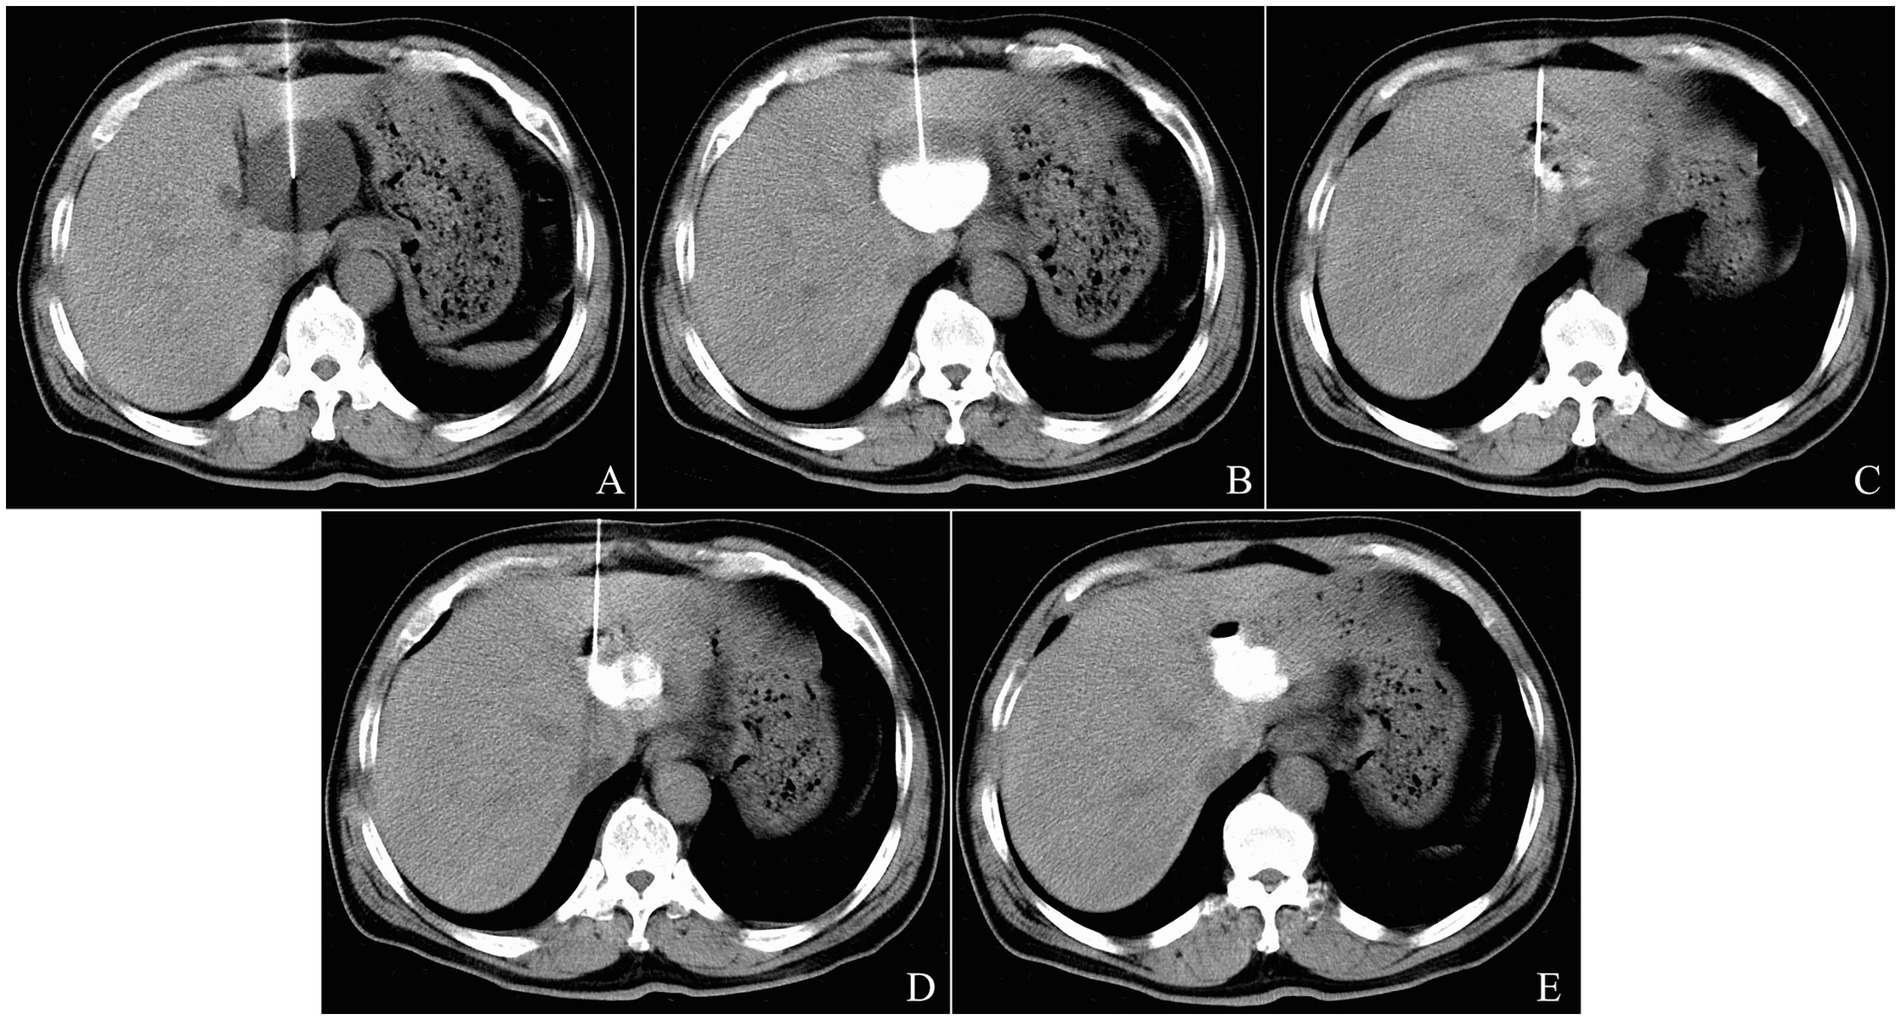

Giant cysts were punctured with a 18 G x 7 cm Catheter Access Percutaneous Entry Needle (Cook Medical, Bloomington, IN, United States) using the Seldinger technique. Once the needle tip reached the cyst cavity and was confirmed by CT scan, a 0.035-inch Terumo guidewire (Terumo Corporation, Tokyo, Japan) was threaded freely through the needle without resistance. A 6-Fr Coons tapered dilator (Cook Medical, Bloomington, IN, United States) was then passed over the guidewire to dilate the puncture acess. Subsequently, a 8.5-Fr Multipurpose Drainage Catheter (Cook Medical, Bloomington, IN, United States) was deployed into the cyst cavity over the guidewire. After confirming the position of the pigtail-shaped tip of the drainage catheter within the cyst cavity by a control CT scan (Figure 3A), the cyst fluid was drainaged continuously for 24 h, until no further outflow was observed. A CT scan on the following day confirmed complete evacuation of the cyst (Figure 3B), after which bleomycin sclerotherapy was performed through the drainage catheter as described above (Figure 3C). Following injection of the sclerosant into the cyst cavity, the drainage catheter was withdraw using a guidewire, and the guidewire was then removed.

Three-panel CT scan images labeled A, B, and C showing percutaneous catheter aspiration for a giant liver cyst. Panel A confirms catheter placement, B shows cyst evacuation, and C post-sclerotherapy.

Figure 3. The operation procedure of CT-guided percutaneous catheter aspiration and bleomycin sclerotherapy for a 64-year-old female patient with a giant liver cyst in polycystic liver disease. After inserting percutaneously a 8.5-Fr drainage catheter into the acyst cavity using the Seldinger technique, the position of the tip of central venous catheter (arrowhead) was confirmed by the control CT scan (A). A recheck CT scan on the next day showed complete evacuation of the cyst (B). After injection of bleomycin solution and removal of pigtail catheter, postprocedure CT scan showed nonoccurrence of sclerosant extravasation (C).